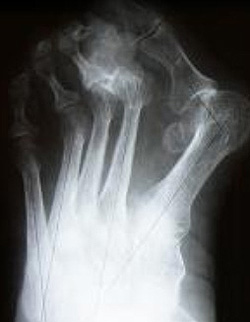

- Рентгенография. На рентгенограммах пальцев стопы просматривается порочное положение фаланг и деформация первого плюснефалангового сустава, нередко выявляются признаки деформирующего артроза. На снимках стопы определяется уменьшение высоты продольного свода.

![Молоткообразный II палец стопы. Hallux Valgus. Рентгенограмма]()